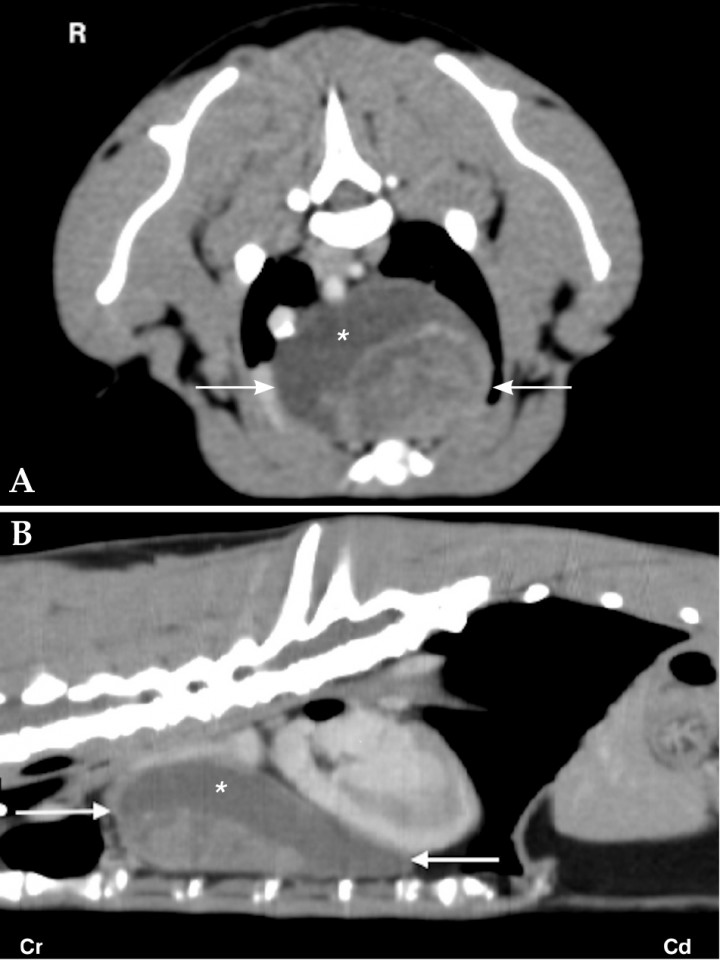

Due to the close relationship of anatomical structures of the neck, cross sectional imaging provides important information of origin and extension of neoplasia in this region. Thyroid gland tumour is the most common neoplasia in the neck and can occur from the base of the tongue to the base of the heart. Although ultrasound is a good screening tool, CT or MRI are indicated if surgical resection is considered. The masses are usually highly vascularized, heterogeneous and can contain regions of dystrophic mineralization. CT findings of carotid body and thyroid tumours are different based on anatomical location. Carotid body tumours have a dorsolateral location to the larynx at the level of the bifurcation of the common carotid artery (Fig. 3A). Thyroid masses are located more caudally (Fig. 3B).[ Mai W, Seiler GS, Lindl-Bylicki BJ et al.: CT and MRI features of carotid body paragangliomas in 16 dogs. Vet Radiol Ultrasound 2015; 56:374-383. [PubMed] , Taeymans O, Penninck DG, Peters RM: Comparison between clinical, ultrasound, CT, MRI, and pathology findings in dogs presented for suspected thyroid carcinoma. Vet Radiol Ultrasound 2013; 54:61-70. [PubMed] ]

<p>(A) 8 year-old Golden Retriever with a carotid body tumour on the right side. Transverse CT soft tissue window post contrast image of the neck at the level of the carotid bifurcation (white arrows) and mandibular salivary glands (black asterisks). There is a poorly demarcated mass (white asterisk) with mild heterogeneous contrast enhancement on the right dorsolateral aspect of the larynx causing lateral displacement of the right carotid arteries. (B) Transverse soft tissue window post contrast image of the neck of a 13 year-old mixed breed dog with a mass at the level of the right thyroid gland (white arrow). The mass shows marked heterogeneous contrast enhancement and a central pinpoint mineralization. The left thyroid gland is unremarkable (black asterisk). R: right.</p>

Figura 3

(A) 8 year-old Golden Retriever with a carotid body tumour on the right side. Transverse CT soft tissue window post contrast image of the neck at the level of the carotid bifurcation (white arrows) and mandibular salivary glands (black asterisks). There is a poorly demarcated mass (white asterisk) with mild heterogeneous contrast enhancement on the right dorsolateral aspect of the larynx causing lateral displacement of the right carotid arteries. (B) Transverse soft tissue window post contrast image of the neck of a 13 year-old mixed breed dog with a mass at the level of the right thyroid gland (white arrow). The mass shows marked heterogeneous contrast enhancement and a central pinpoint mineralization. The left thyroid gland is unremarkable (black asterisk). R: right.